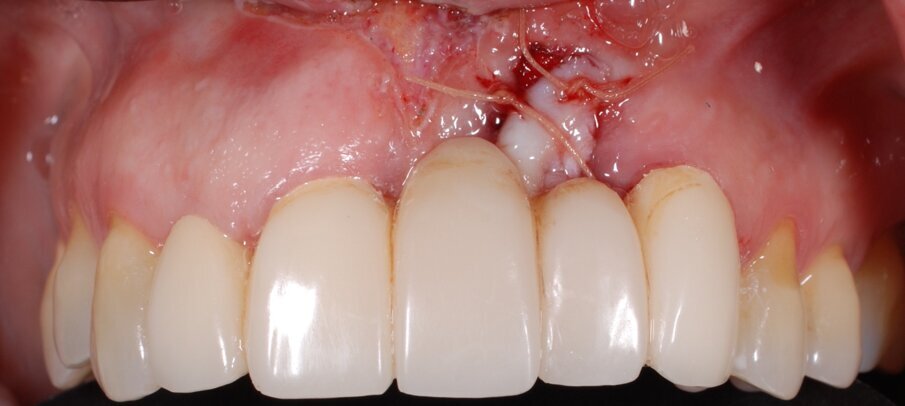

In questo articolo presentiamo un caso clinico che dimostra come il posizionamento improprio di un impianto può rendere impossibile la riabilitazione protesica, che richiede una nuova pianificazione chirurgica e riabilitativa per ottenere l’estetica desiderata. La paziente si presenta alla nostra osservazione con una riabilitazione protesica incongrua, con flangia in resina, a supporto dentale ed implantare, con la presenza di un impianto in posizione 2.1 vestibolarizzato e con l’emergenza nel fornice, in mucosa alveolare. Dalla valutazione della Tac si evince la posizione errata dell’impianto e la perdita consistente in senso trasversale della compagine ossea (Figg. 1, 2). Pertanto si opta per il seguente piano di trattamento che prevede: rimozione dell’impianto e preparazione protesica dell’elemento 2.3, confezionamento di un primo provvisorio a supporto dentale che servirà a guidare la guarigione dei tessuti (Figg. 3-7). A distanza di 4 mesi si procede a un innesto epitelio connettivale libero con prelievo dal palato per compensare il gap dei tessuti molli in senso trasversale, quindi viene ribasato il provvisorio in modo tale da favorire la guarigione dei tessuti (Figg. 8-11). A 9 mesi dalla maturazione dei tessuti si procede alla finalizzazione protesica fissa a supporto dentale (Figg. 12-14).

Fig. 7 - Applicazione del provvisorio dopo preparazione protesica del 2.3 e frenulectomia laser.

Fig. 8 - Innesto di epitelio connettivale libero dopo 4 mesi dalla guarigione del sito implantare.